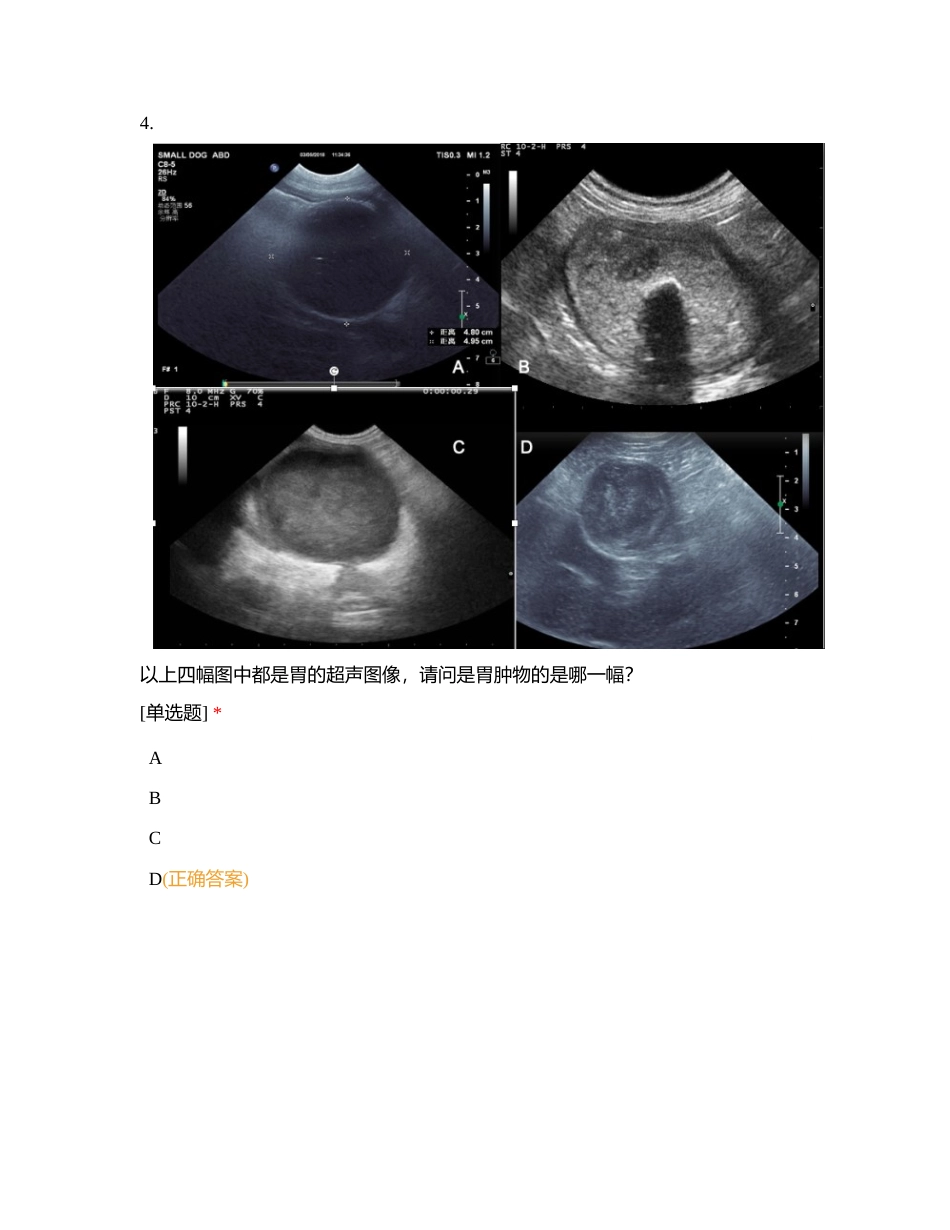

梅奥宠物医学中心-胃肠超声影像在线侦测[复制]您的姓名: [填空题] *_________________________________1. 关于兽医临床胃肠道超声检查,以下说法正确的是? *受检动物需禁食 12 小时(正确答案)可以给予灌...